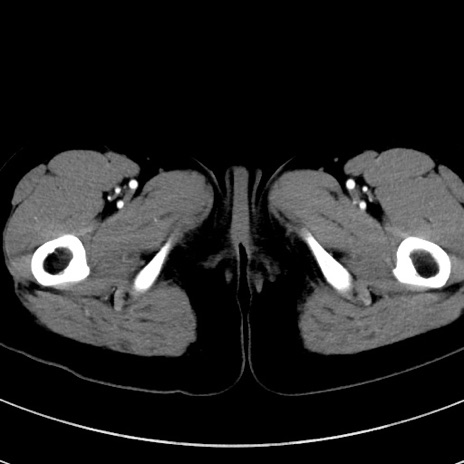

冠状断像

症例17(横断像)

【症例】20歳代女性

【主訴】嘔吐、下腹部痛

【現病歴】昨日夕食後に嘔吐し下腹部痛が出現。本日になっても嘔吐持続し改善しないため来院。

【身体所見】意識清明、BT 37.2℃、BP 108/67mmHg、腹部:平坦、やや硬、下腹部正中から右にかけて圧痛あり、反跳痛軽度あり、tapping pain(+)。

【データ】WBC 13600、CRP 14.94